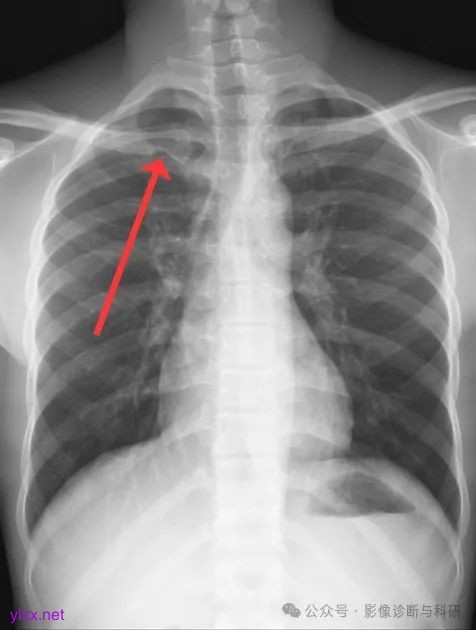

右侧锁骨菱形窝凹陷